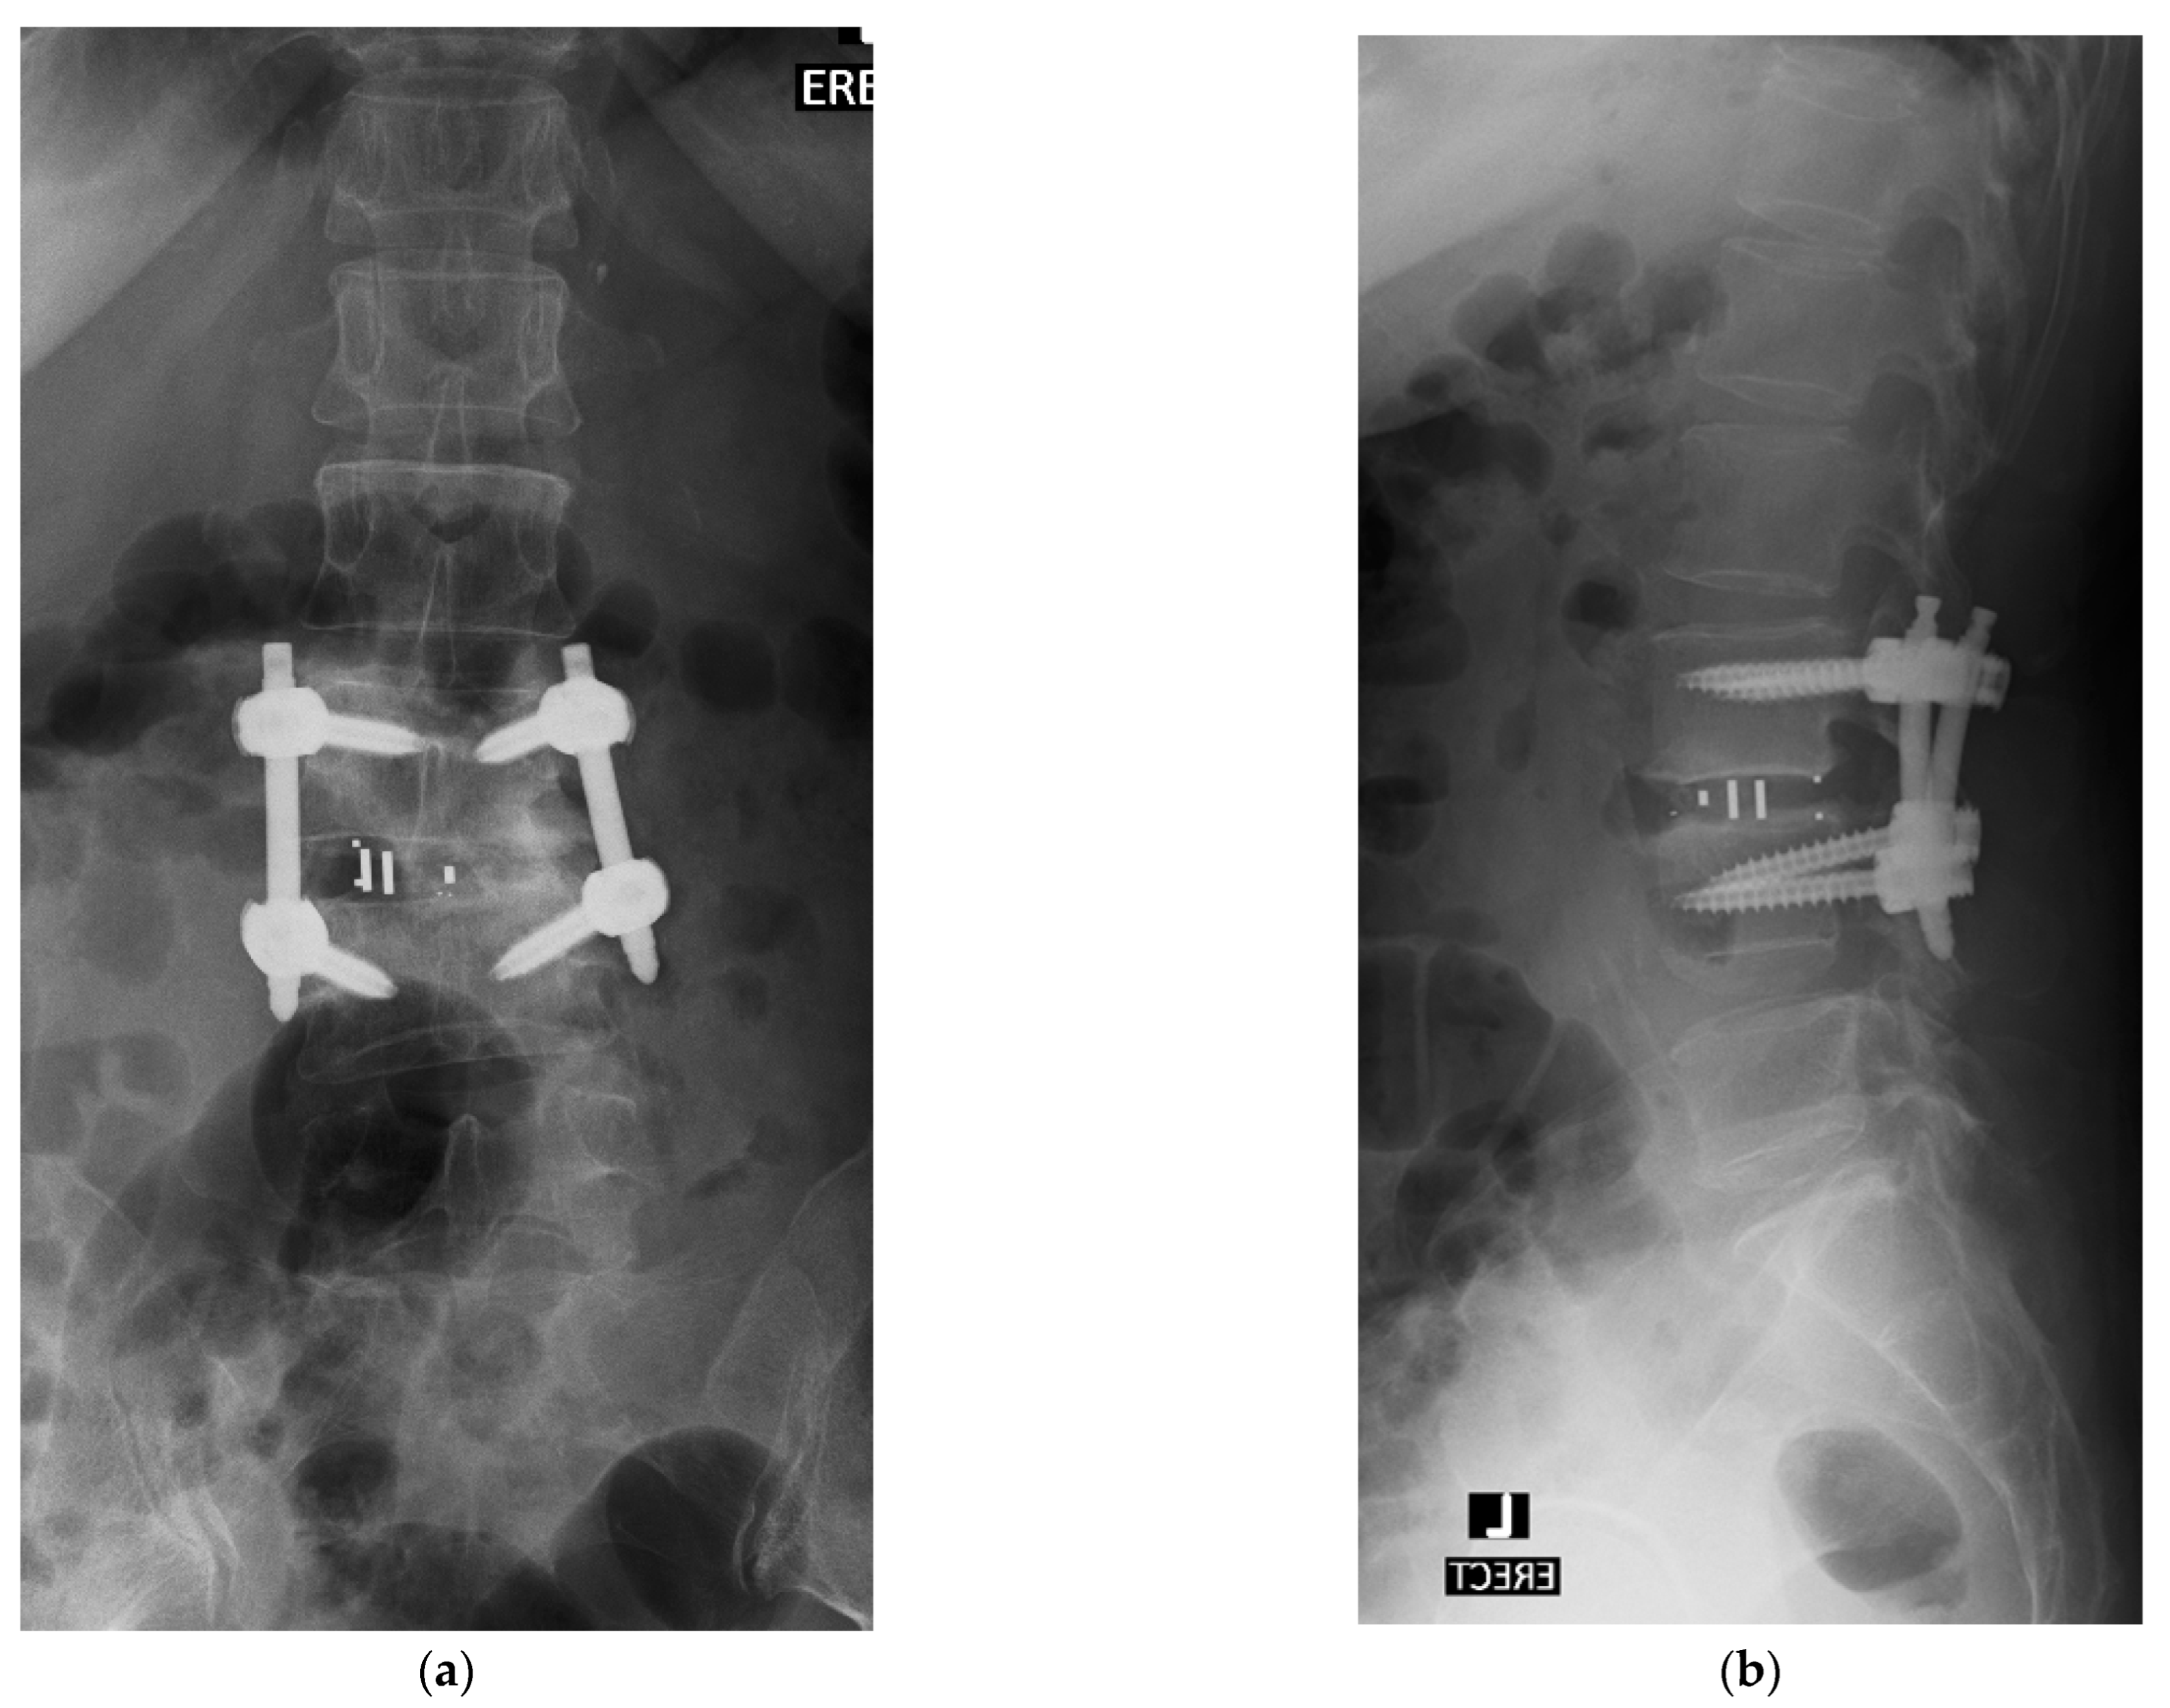

3.9. Percutaneous Posterior Instrumentation under Fluoroscopic Guidance

4.1. Case 1: Madam M

4.2. Case 2: Madam R

4.3. Case 3: Madam M